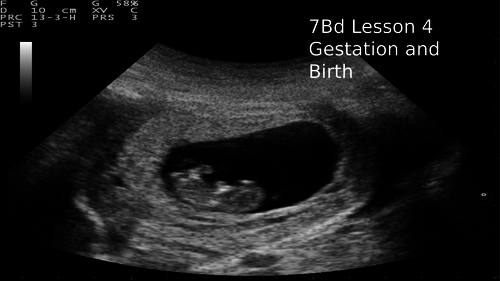

A complete set of PowerPoints and worksheets for the unit 7B reproduction.